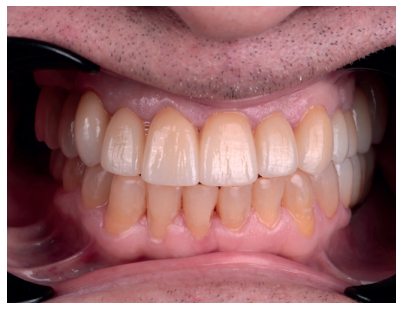

Pasados tres meses de la colocación de los implantes, se realizó un control clínico y radiográfico, se procedió a realizar la segunda fase y se derivó al Máster de Prótesis Bucofacial para continuar con el tratamiento. Se planificó el caso de manera totalmente digital. La arcada superior se rehabilitó con coronas de circonio, mientras que en la arcada inferior se realizaron coronas y puentes de circonio sobre implantes, incrustaciones de disilicato de litio y reconstrucciones de los bordes incisales inferiores con resinas compuestas (Figura 13).

En la revisión realizada a los seis meses, el paciente ha recuperado la función y la estética y está plenamente satisfecho con el resultado (Figura 14.) La radiografía periapical de control de los implantes cargados presenta buenos niveles óseos y una completa integración del injerto de dentina (Figura 15).